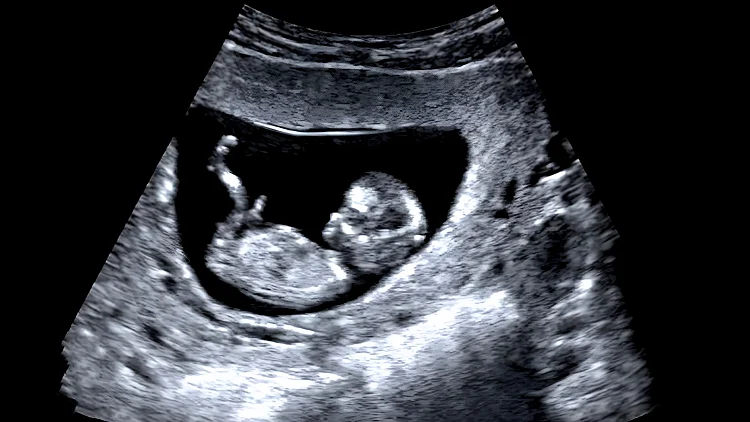

אפליקציית המסחר היפנית Mercari הודיעה כי תחסום כל מודעה המציעה למכירה תמונת אולטרסאונד של עוברים. על פי ההערכות, הצילומים משמשים להונאת היריון

יפן: משתמשים באפליקציית המסחר הפופולרית Mercari הבחינו לאחרונה בגל של מודעות יוצאות דופן שהציעו למכירה תמונות אולטרסאונד שח עוברים, שהוצעו למכירה במחירים של מאות עד אלפי ין.

הכל החל כאשר גולש פרסם ב-13 באוגוסט צילום מסך של מודעות ובהן תמונות אולטרסאונד למכירה, ותהה מדוע שמישהו ירצה לרכוש תמונות אולטרסאונד של זרים. "השימוש היחיד בהן הוא הונאת היריון", כתב בפוסט שהפך לוויראלי.

המחירים שנראו ברשת נעו סביב 2,000 ין (כ-50 ש"ח), ולעיתים אף פחות. בתגובה לסערה, הוחלט ב-Mercari לחסום מכירה של צילומי אולטסראונד, אם כי בחרו שלא לפרט את הסיבה המדויקת לאיסור.